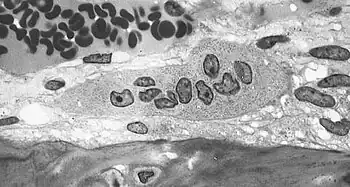

Pathogenesis

Although the methods of action are not yet completely understood, it is hypothesized that medication-associated osteonecrosis of the jaw is related to a defect in jaw bone healing and remodelling.

The inhibition of osteoclast differentiation and function, precipitated by drug therapy, leads to decreased bone resorption and remodelling.[31][39] Evidence also suggests bisphosphonates induce apoptosis of osteoclasts.[40] Another suggested factor is inhibition of angiogenesis due to bisphosphonates; this effect remains uncertain.[41][42][43] Several studies have proposed that bisphosphonates cause excessive reduction of bone turnover, resulting in a higher risk of bone necrosis when repair is needed.[44][45][46]

It is also thought that bisphosphonates bind to osteoclasts and interfere with the remodeling mechanism in bone. To be more specific, the drug interferes with the cholesterol biosynthesis pathway through the inhibition of farnesyl diphosphate synthase. Over time, the cytoskeleton of the osteoclasts loses its function and the essential border needed for bone resorption does not form.[7] Like aminobisphosphonates, bisphosphonates have shown to have antiangiogenic properties. Therefore, effects include an overall decrease in bone recycling/turnover as well as an increased inhibition of the absorptive bone abilities.